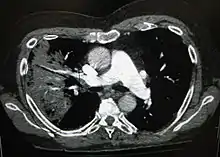

تصاویر اشعه ایکس از سینه پهلو به سینه پهلو لختهای، سینه پهلو برونشی (همچنین با عنوان سینه پهلو بخشی شناخته میشود) و سینه پهلو بینابینی قابل طبقهبندی است.[41] سینه پهلو اکتسابی باکتریایی، بهطور معمول تجمع ریوی در یک لوب سگمنتال ریه را نشان میدهد که به آن سینه پهلو لختهای میگویند.[21] با این حال ممکن است یافتهها متفاوت باشند و الگوهای دیگری در انواع دیگر سینه پهلو شایع است.[21] سینه پهلو آسپیراسیون ممکن است با تیرگی دوطرفه و عمدتاً در پایین ریهها و در سمت راست وجود داشته باشد.[21] تصاویر رادیوگرافی سینه پهلو ویروسی ممکن است طبیعی به نظر برسد، بیش از حد متورم باشد، مناطق لکهدار در هر دو طرف مشاهده شود، یا شبیه سینه پهلو باکتریایی، تجمع لختهای را نشان دهد.[21] ممکن است نتایج رادیولوژی در مراحل اولیه بیماری مشاهده نشود، بهویژه در صورتی آب بدن از دست رفته باشد؛ یا ممکن است تفسیر آن در کسانی که چاق هستند یا سابقه بیماری ریوی دارند، دشوار باشد.[12] سیتی اسکن میتواند اطلاعات بیشتری را در موارد نامشخص در اختیار قرار دهد.[21]